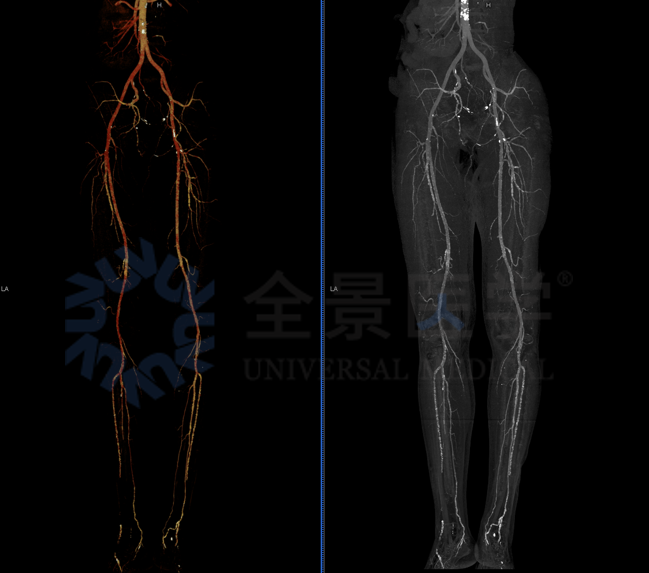

53 岁,糖尿病治疗中

双下肢 CTA 显示双下肢动脉硬化,其中双侧胫前动脉、胫后动脉、腓动脉局限性轻中度狭窄,双侧足背及足底远端动脉稀疏。